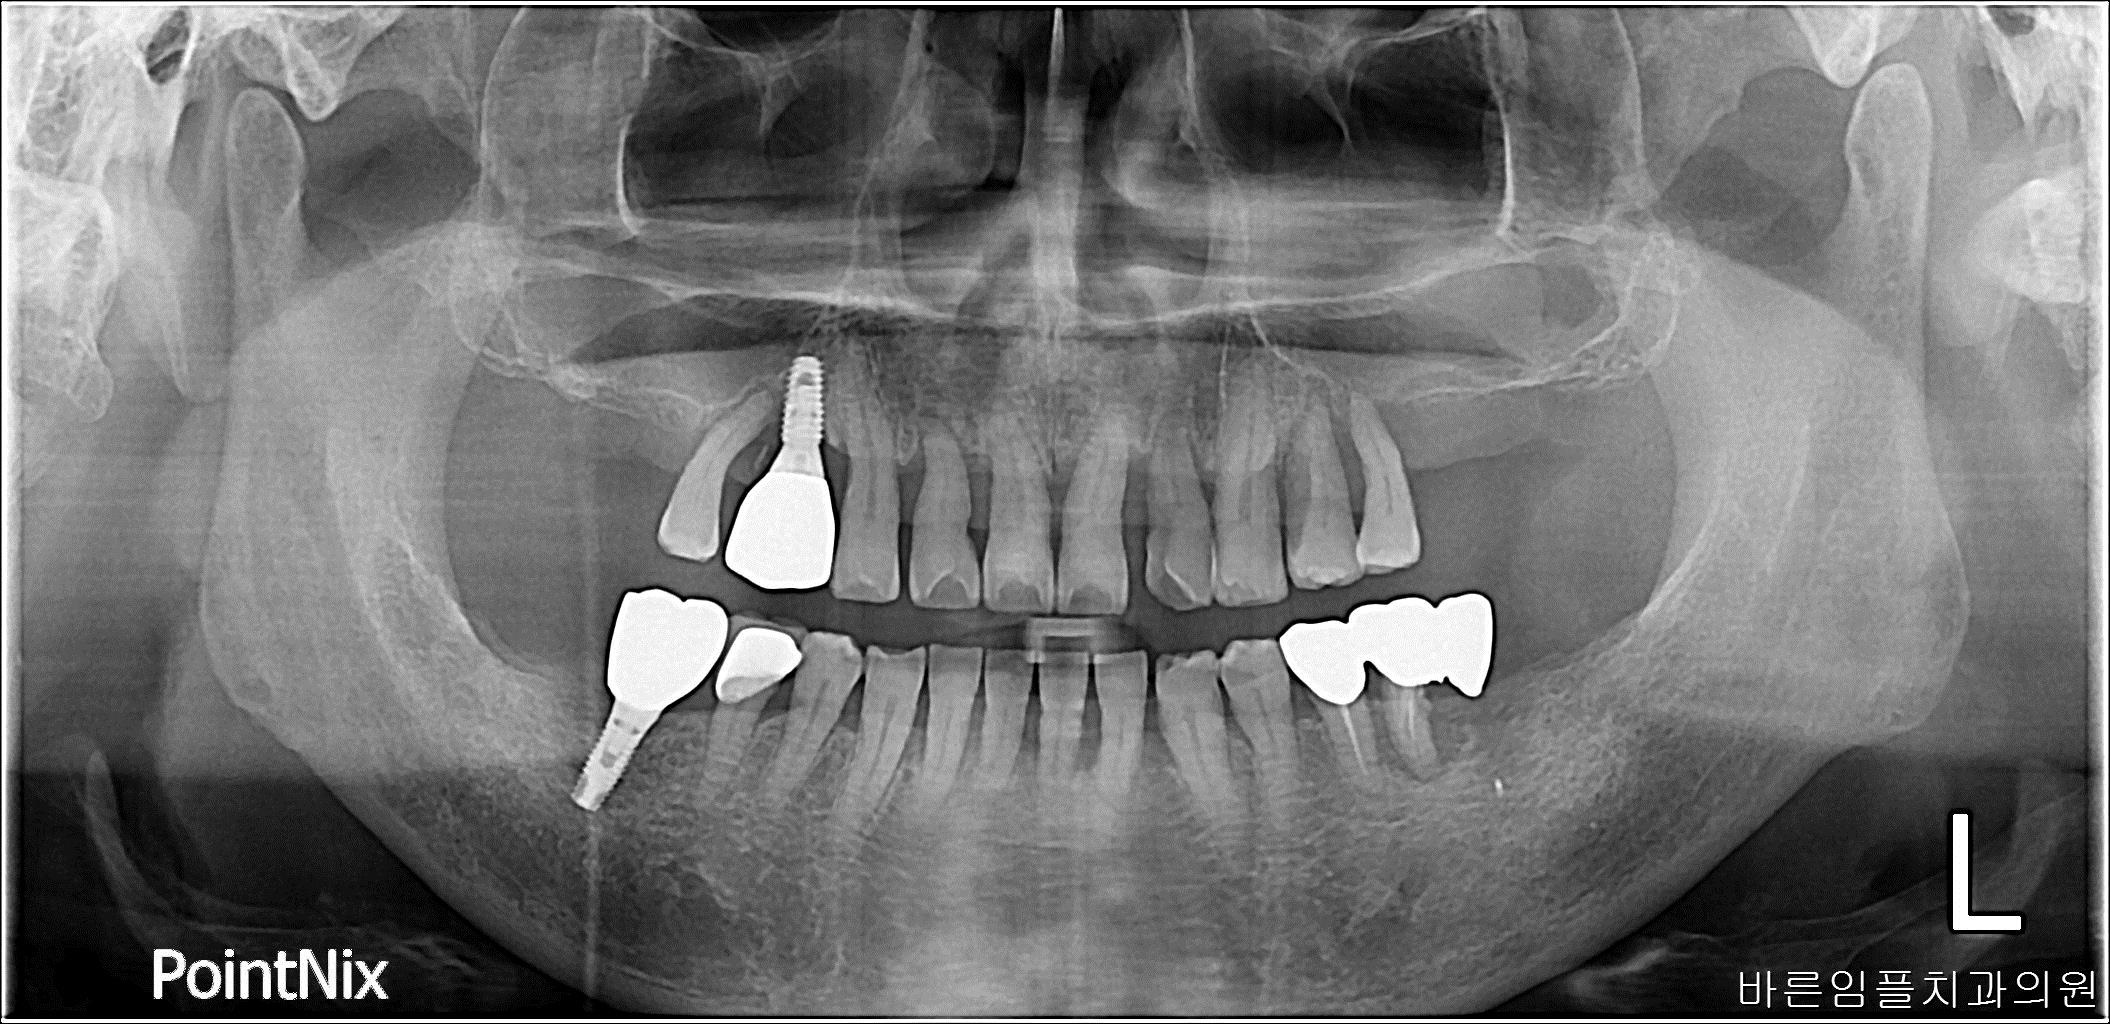

2018-03-02

김ㅇㅇ

Before